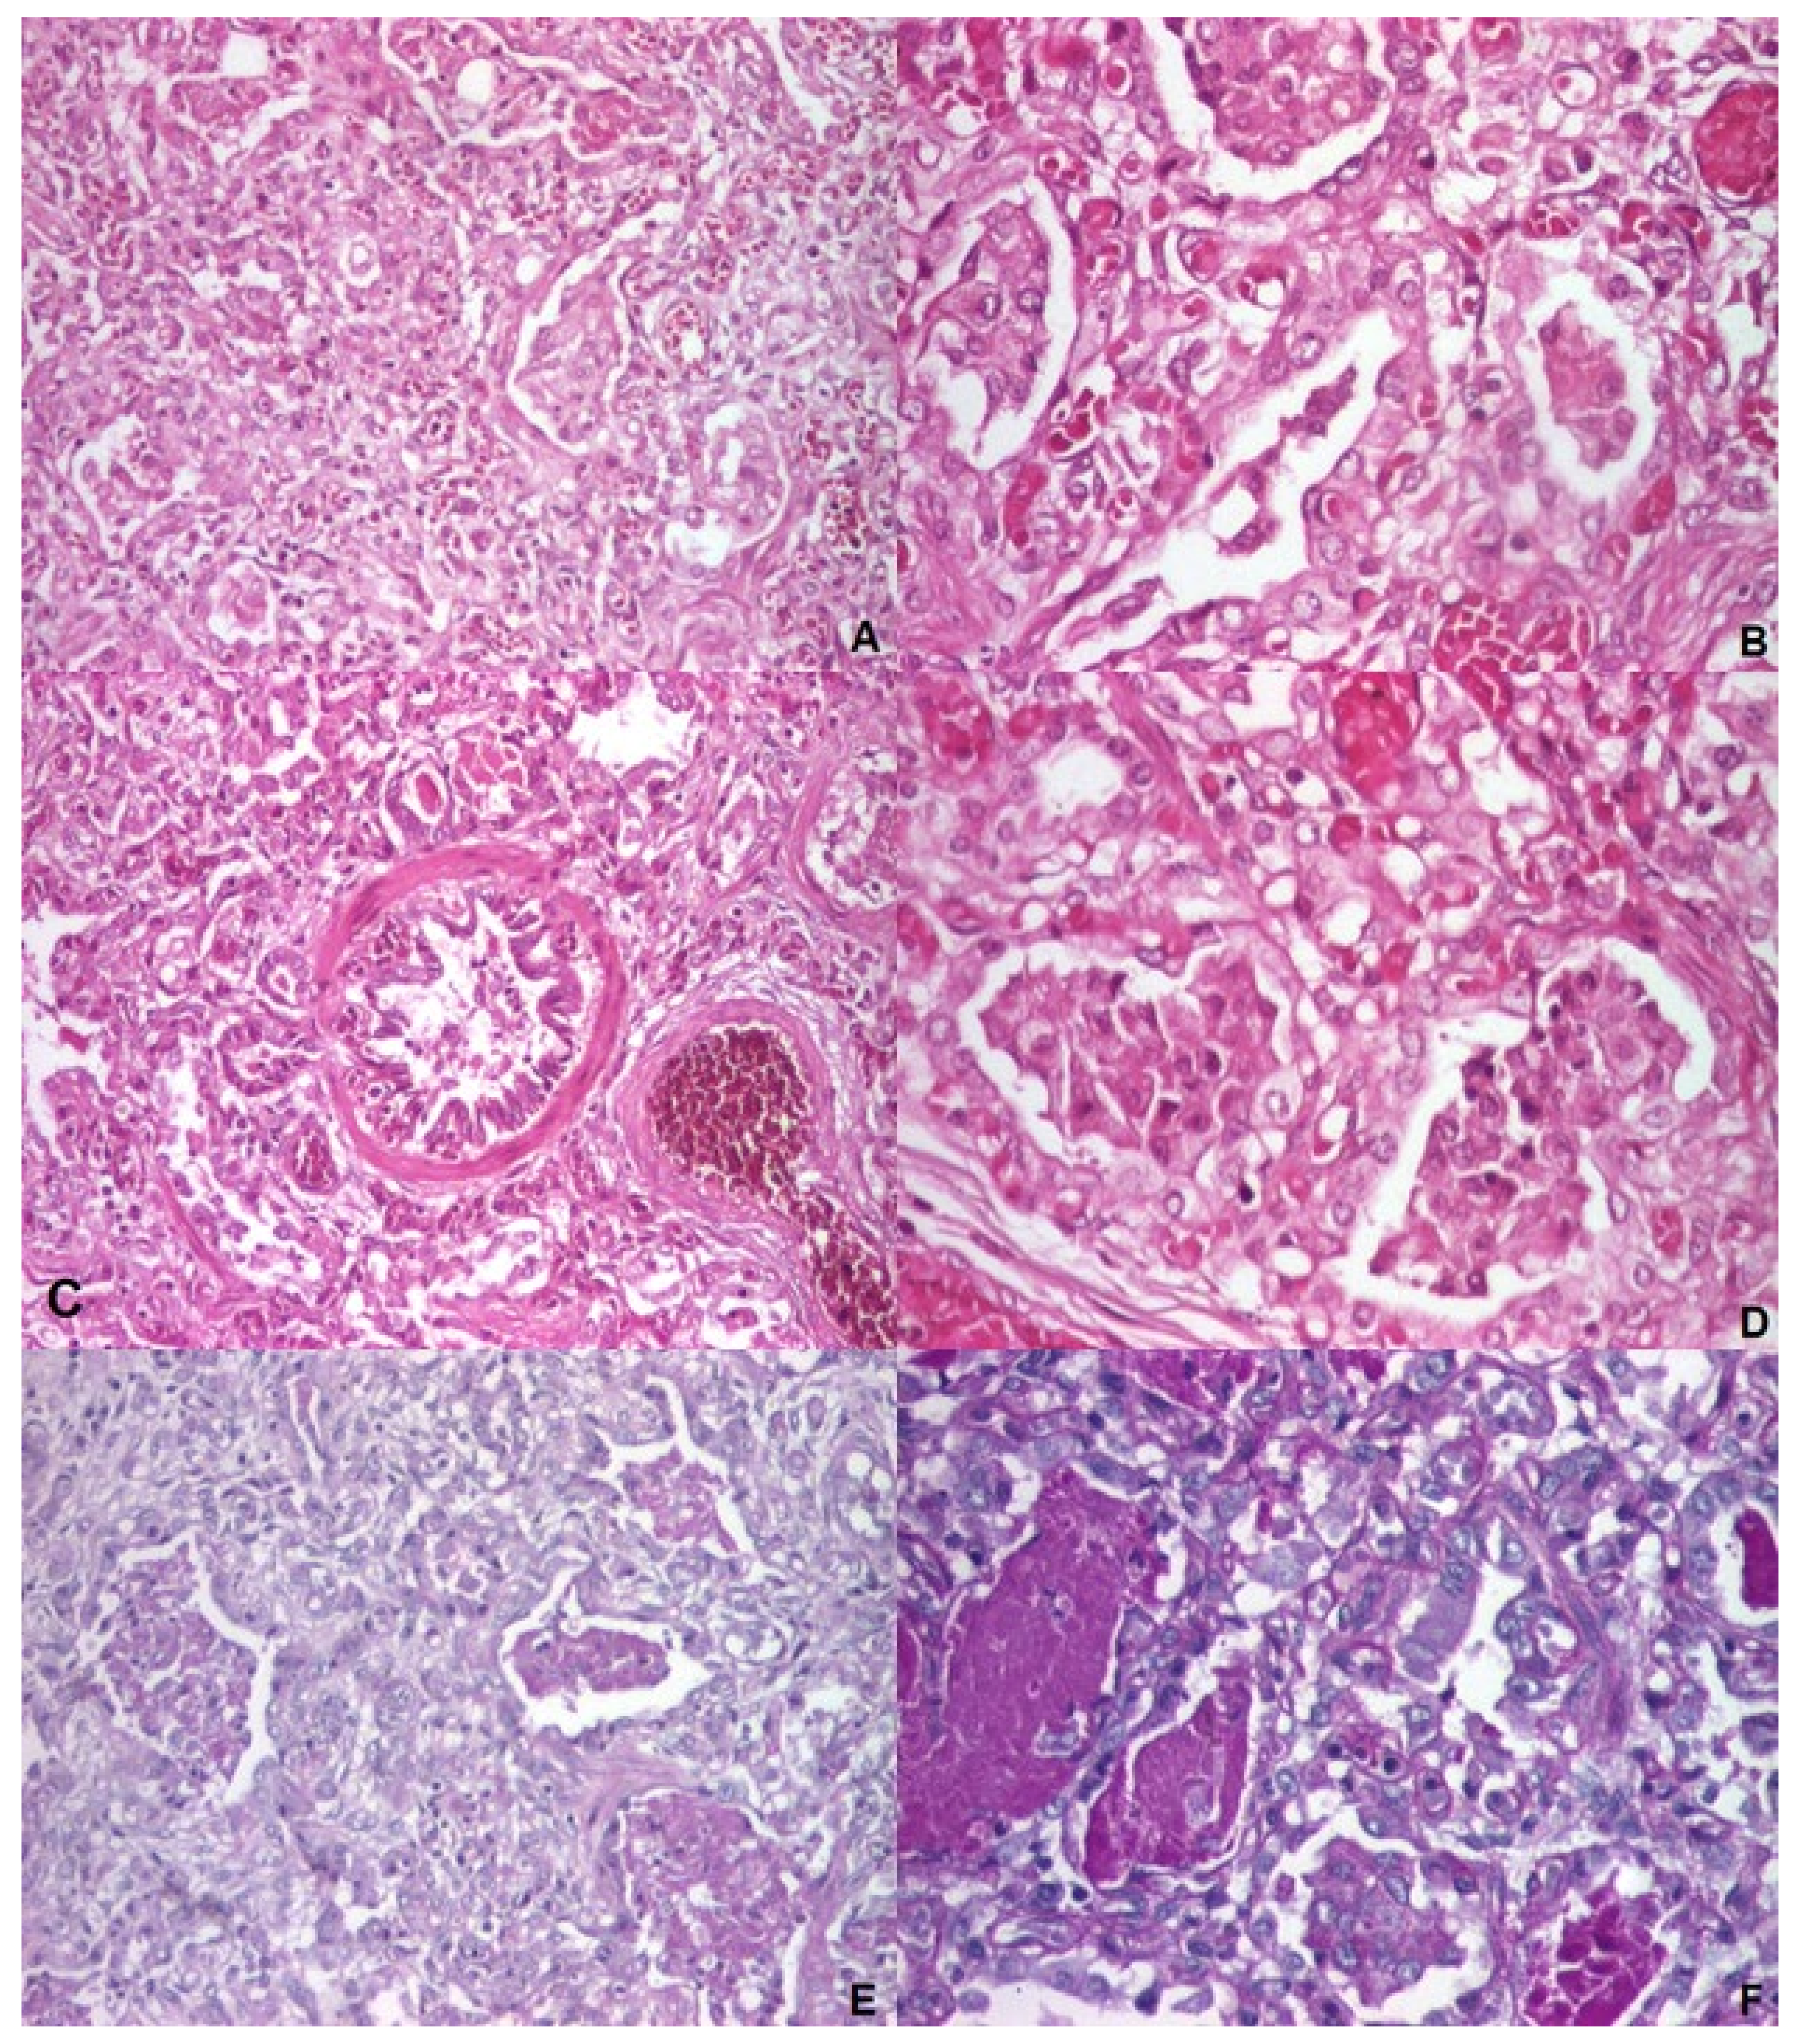

| 10. | Ognean et al., 2024 (this study) | Male | 37 weeks | 2700 g | Severe nRDS – advanced respiratory support (HFOV), prednison, azithromycin, hydroxychloroquine treatment | Thoracic x-ray – ground glass homogeneous opacity | CPI pattern with lobular remodeling, prominent AEC II hyperplasia, focal PAP pattern and extensive DIP-like areas, alveolar proteinosis | N/A | p.Arg280Cys (R280C, c.838C>T, rs201299260)/heterozygous/paternal origin | p.Gln233ter (Q233X, Q233*)heterozygous/maternal origin | SFTPB p.Val267Ile | No, healthy parents, one healthy sibling despite carrying p.Gln233ter and SFTPB p.Val267Ile variants | Died at 77 days of life | Current case report |